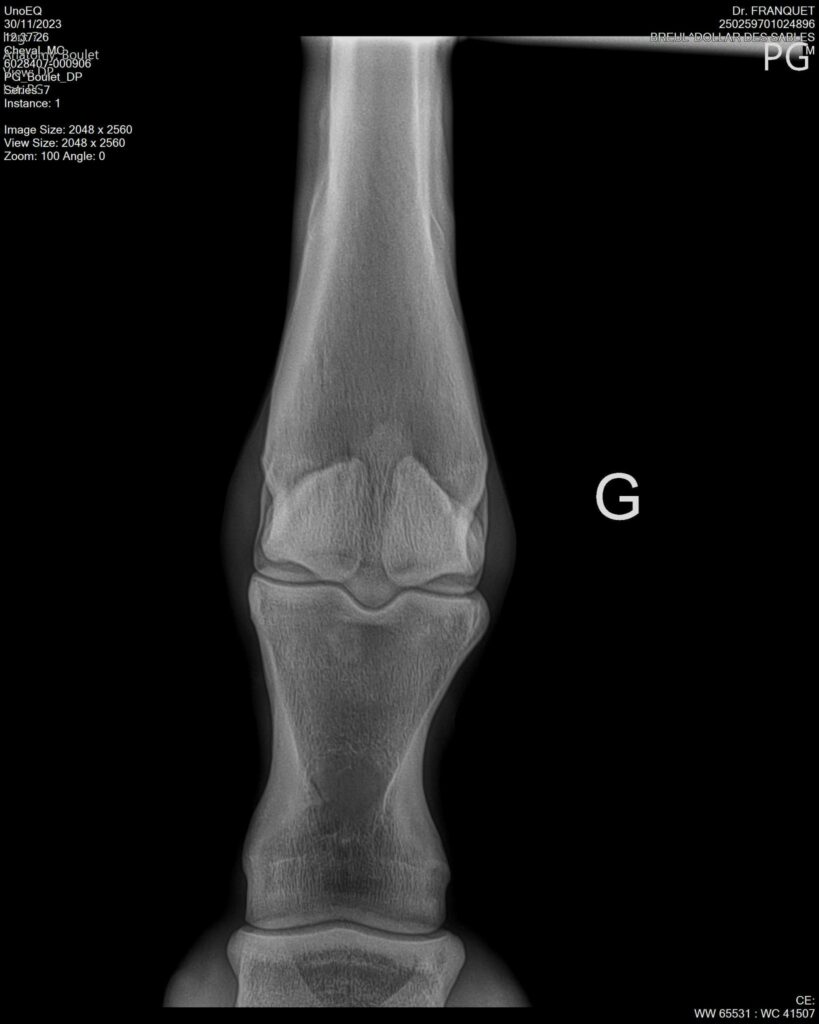

DOLLAR DES SABLES, Selle Français, hongre, 12 ans par DOLLAR DE MURIER x ABKE (ACORADO). Classé 135 avec professionnel à fait 125 avec amateur, récemment classé sur amateur 1GP 120. Très beau modèle ! Gentil cheval, respectueux avec des moyens et du sang. Transport OK, maréchalerie OK, santé RAS, Bilan clichés radios OK.

RADIOS